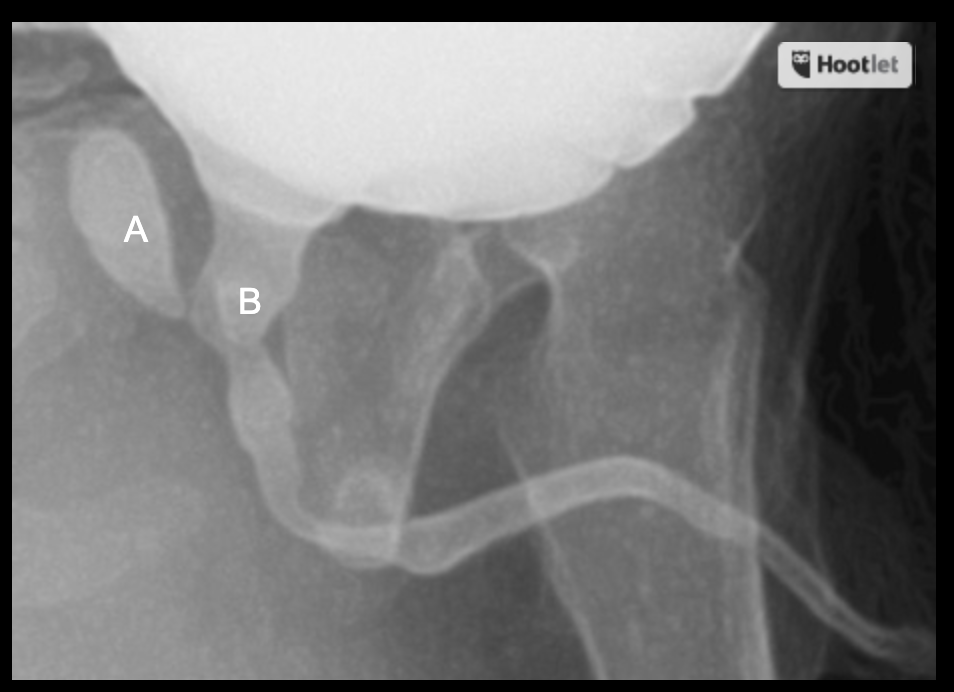

What is this?

What are the labeled structures?

A. Utricle

B. Prostatic urethra

Utricle: müllerian duct remnant; blind-ending pouch in midline

https://caps.nationwidechildrens.org/radiology/atlas/Urethra_Atlas/Prostatic_utricle.html

The prostatic utricle is a small, epithelium-lined diverticulum of the prostatic urethra. It is located in the verumontanum between the two openings of the ejaculatory ducts and extends backward and slightly upward for a very short distance within the medial lobe of the prostate.

It is a normal anatomic variant representing the remnant of the fused caudal ends of the Müllerian ducts, and thus is the homolog of the female vagina and uterine cervix.